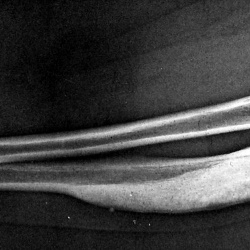

Деформация предплечья давно. Болей и других мешающих факторов нет.